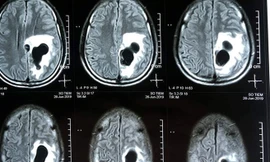

TPO - Kết quả chụp CT não của người đàn ông 38 tuổi tại Nghệ An cho thấy có 5 ổ sán nằm rải rác trong não, trong đó có một ổ sán lớn trên đỉnh của bệnh nhân gây phù não.